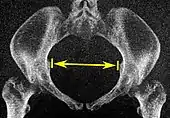

| Intertuberous diameter | ![]() |

![]() Axial plane |

The closest bony points of the ischial tuberosities | 10 to 12 cm.[6] | |